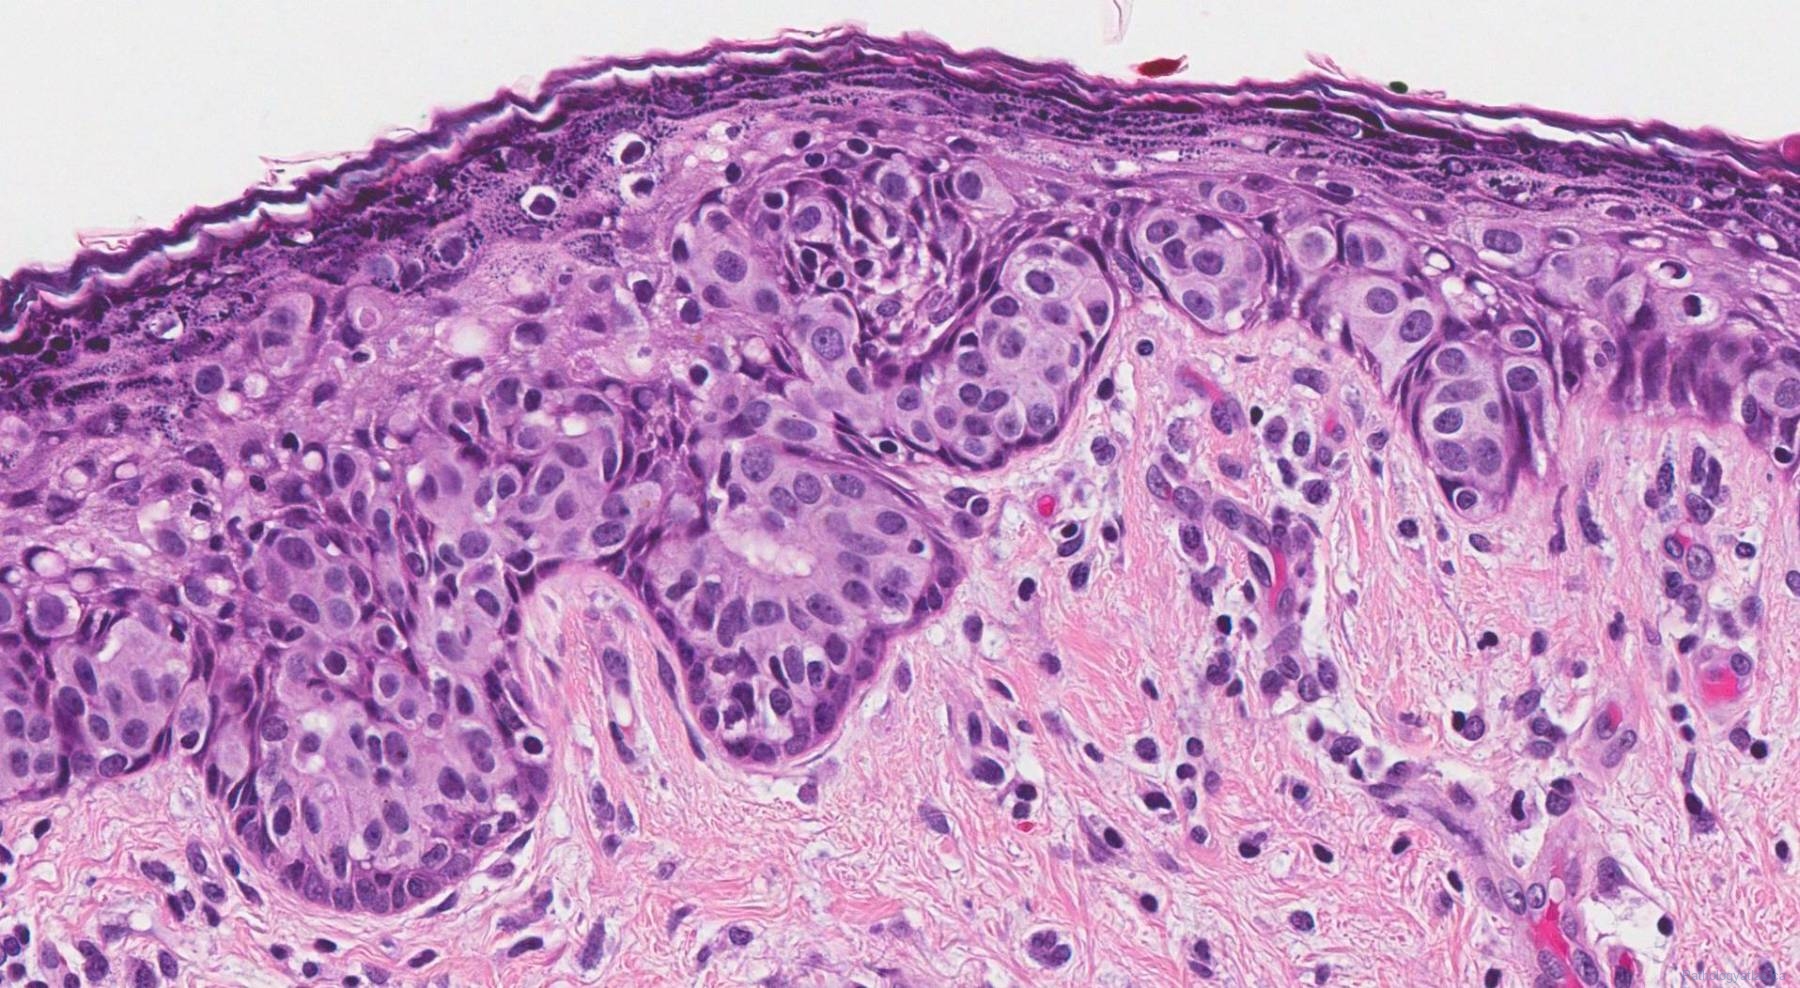

Фотографии опухоли медуллярной аденокарциномы

Раздел: Снимки-откровения